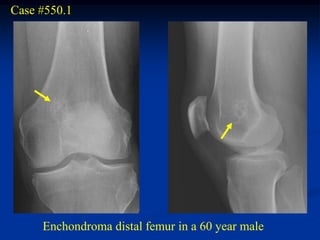

Case #550.1

Enchondroma distal femur in a 60 year male